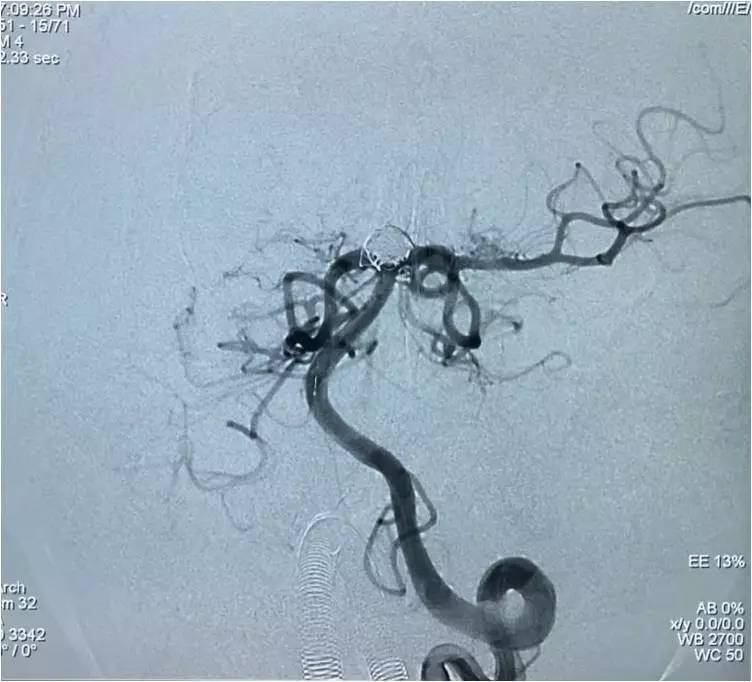

下面是术后各个角度的左椎动脉造影,可见基底动脉顶端动脉瘤和左小脑上动脉瘤完全栓塞,载瘤动脉畅通。基底动脉顶端动脉瘤的子瘤终于被消灭。

▼纯正位。

▼侧位。